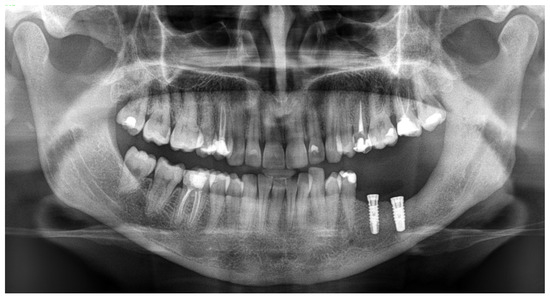

Figure 4. An immediate early panoramic radiograph with very good and stable outcomes. After tumor removal, ostectomy, local resection, and reconstruction with allogenic bone graft and titanium plates, the result is very good. Because a very thin healthy bone layer was remaining, additional IMF—intramaxillary—screws (titanium 2.0 plates, Medartis, Basel, Switzerland) were used to maintain stable occlusion, avoid any fracture, and decrease the possibility of any wound dehiscence and irritation. It is worth noting and remembering that CGCG should be differentiated from the following lesions and tumors: brown tumors in PHP, peripheral form of CGCG (PGCG), giant cell tumor, lesions from cherubism, non-ossifying fibromas, and ABCs—aneurysmal bone cysts—or even ameloblastoma [4,5]. Radiological differentiation should also include myxoma/odontogenic-myxoma (OM), ameloblastic fibroma (AF), and ossifying fibroma (OsF); however, the additional presence of calcifying and bone masses inside the lesions, with an irregular border and lesion shape, improves the diagnosis. Some atypical cyst formation, spread, and occurrence in the jaw bone might also mimic other tumors or lesions, which is why it is crucial to evaluate each atypical case carefully [6]. This case underlines how similar radiological appearances can be seen in various different tumors, and how not only a biopsy but bone makers with SPECT examination can improve the diagnostics. Each BT and CGCG can be misdiagnosed, which is why improved histopathology is important w a larger sample. This case excluded PHP; however, more extensive histopathological evaluation concluded an occurrence of typical brown tumor characteristics for a long but slow growth, but without any significant correlation between the endocrine and calcium–phosphate markers, which is quite unusual.

Diagnostics 15 02038 g004